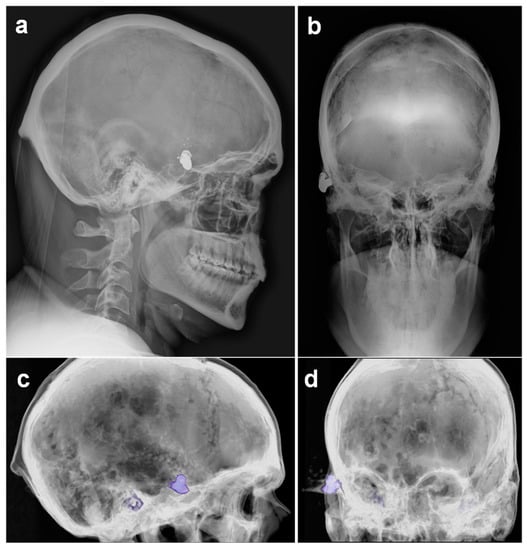

A Suicide Attempt with a Velo-Dog Pocket Revolver in an Alleged Victim of Carjacking

2. Case Report